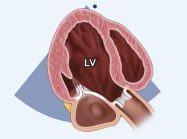

| 2.1. Mặt cắt trục dài cạnh ức với depth sâu

Cửa sổ siêu âm cạnh ức

Mặt cắt trục dài cạnh ức Đầu dò đặt tại bờ trái xương ức với marker hướng lên vai phải của bệnh nhân. |

Khoang màng ngoài tim Khoang màng phổi | |||||

| 2.2. Mặt cắt trục dài cạnh ức khu trú vào thất trái

Cửa sổ siêu âm cạnh ức

Mặt cắt trục dài cạnh ức Đầu dò đặt tại bờ trái xương ức với marker hướng lên vai phải của bệnh nhân. Chùm siêu âm đặt vuông góc với thất trái. |

Nhĩ trái (LA)

Van hai lá (MV) Thất trái (LV) Đường ra thất trái (LVOT) Van động mạch chủ (AV) Vách liên thất (IVS) Thất phải (RV) |